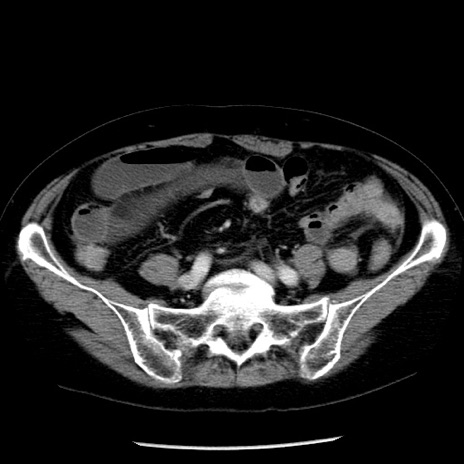

症例13(横断像)

【症例】70歳代女性

【主訴】腹痛、嘔吐

【現病歴】15時間程前(昨晩)より腹痛あり。今朝になっても症状の改善なく、嘔吐あり。腹痛も増悪あり、救急外来受診。

【既往歴】子宮癌全摘術後

【身体所見】意識清明、BP 121/72mmHg、P 74bpm、SpO2 100%(RA)、腹部:平坦・軟、腸雑音ほぼ聴取せず。下腹部・心窩部・臍左上に圧痛あり。反跳痛なし。

【データ】WBC 10600、CRP 0.15